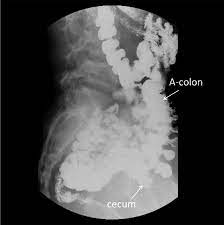

However stenosis with concentricity of the fold was observed in the cecum which was shifted upward and to the left. The patients symptoms resolved quickly after colonoscopic reduction and elective laparoscopic surgery was performed 18 days after admission. This report details the case of a patient with a mobile cecum associated with hEDS.

The patients symptoms resolved quickly after colonoscopic reduction and elective laparoscopic surgery was performed 18 days after admission. A planned surgery is not fun but an emergency surgery for a twisted colon would be even worse. Based on these findings we diagnosed cecal volvulus caused by mobile cecum syndrome. On the other hand a chronic form of mobile cecum syndrome which is the most common form reported a history of intermittent crampy abdominal pain distension and constipation. However it may be present as a precursor of frank cecal volvulus in approximately 50 per cent of the cases. 102 patients were followed up to 15 years after the operation. Abstract Five cases of mobile cecum syndrome are presented. Ehlers-Danlos syndrome hypermobility type EDS-HT mobile cecum ptosis laparoscopic. The following symptoms may be experienced with cecal volvulus.